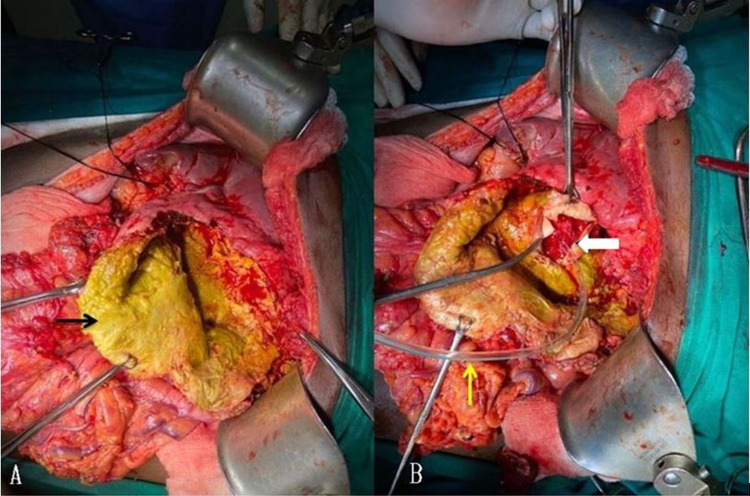

A meticulous search for the CBC was done. A cholecystectomy was performed. The cystic duct’s cannulation was done, the catheter advanced into the hepatic duct, and CBD was blocked with a clamp. Propofol was injected through the catheter. Four CBCs were very well demonstrated with leakage of the propofol through the inner surface of the residual cyst wall. All the communications were primarily sutured with polypropylene. A drain was placed into the residual cyst cavity, and omentopexy was done. The cystoduodenal fistula was visualized during the cystectomy (Figure 5).

As the size of the fistula was less than 5 mm, it was closed primarily with an omental patch.